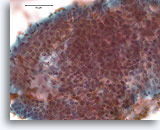

Papillair carcinoom, Borst FNA, Celblok.

Deze kleuring met gladde spier-actine toont enige stromale myofibroblasten, maar geen myoepitheliale cellen buiten de grenzen van het basaalmembraan van de fibrovasculaire kernen in het papillaire carcinoom dat wordt afgebeeld in afbeelding 39-47.

40X

Papillair carcinoom, Borst FNA, Celblok.

Deze kleuring met gladde spier-actine toont enige stromale myofibroblasten, maar geen myoepitheliale cellen buiten de grenzen van het basaalmembraan van de fibrovasculaire kernen in het papillaire carcinoom dat wordt afgebeeld in afbeelding 39-47.

40X

Papillair carcinoom, Borst FNA, Celblok.

Een kleuring met calponine voor myoepitheliale cellen is vaak gemakkelijker te interpreteren dat een immunokleuring met gladde spier-actine. Dezelfde patiënt als in afbeelding 48 toont geen myoepitheliale cellen.

40X

Papillair carcinoom, Borst FNA, Celblok.

Een kleuring met calponine voor myoepitheliale cellen is vaak gemakkelijker te interpreteren dat een immunokleuring met gladde spier-actine. Dezelfde patiënt als in afbeelding 48 toont geen myoepitheliale cellen.

40X

Papillair carcinoom, Borst FNA, Celblok.

Een immunokleuring met p63 voor myoepitheliale cellen is ook negatief bij de patiënt die in voorgaande afbeeldingen getoond is; dit steunt de diagnose van papillair carcinoom.

10X

Papillair carcinoom, Borst FNA, Celblok.

Een immunokleuring met p63 voor myoepitheliale cellen is ook negatief bij de patiënt die in voorgaande afbeeldingen getoond is; dit steunt de diagnose van papillair carcinoom.

10X